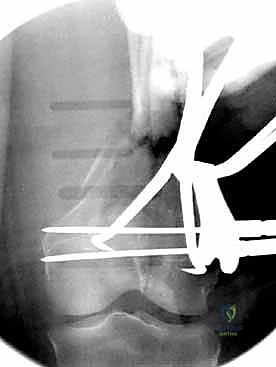

قبل بدء الجراحة، يتم رسم خطة دقيقة. يتم وضع المريض على طاولة العمليات المجهزة بأشعة (C-Arm) لضمان التصوير الفوري أثناء الجراحة.

المرحلة الثالثة: إرجاع العظم (Reduction)

هذه هي الخطوة الأكثر أهمية. يقوم الدكتور هطيف بإعادة القطع العظمية المكسورة إلى مكانها التشريحي الأصلي. إذا كان الكسر ممتداً داخل المفصل، يتم تثبيت السطح المفصلي أولاً باستخدام مسامير دقيقة لضمان سطح أملس يمنع الاحتكاك والخشونة مستقبلاً.